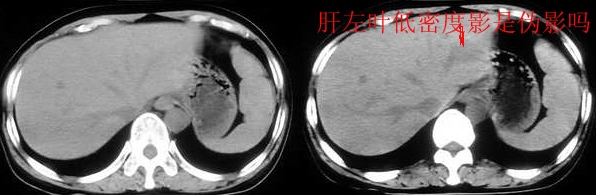

[br]请问战友,肝左叶低密度影和增强后杂乱无章的血管是什么?这是正常的吗?

以下是引用向医生在2005-11-3 21:54:00的发言:[br][br] 我觉得这例除了胆囊结石可以肯定外,肝左叶低密度区考虑为病灶尚不可靠。[br] 在b超下,早期肝脓肿者肝内见较强回声,界限欠清、模糊、形态不规则,如果有坏死液化才会出现低回声,而本例超声下已见低回声,如果真是这种情况的话就是说明病灶内已有坏死液化,这些液化区在ct增强下应该表现为低密度影,本例增强并无这样改变,所以b超的结果可不可靠值得怀疑。[br] 胆囊结石合并胆囊炎也可出现畏寒、发热及白细胞增高等,抗炎治疗后也可症状缓解,不一定非要用肝脓疡来解释。